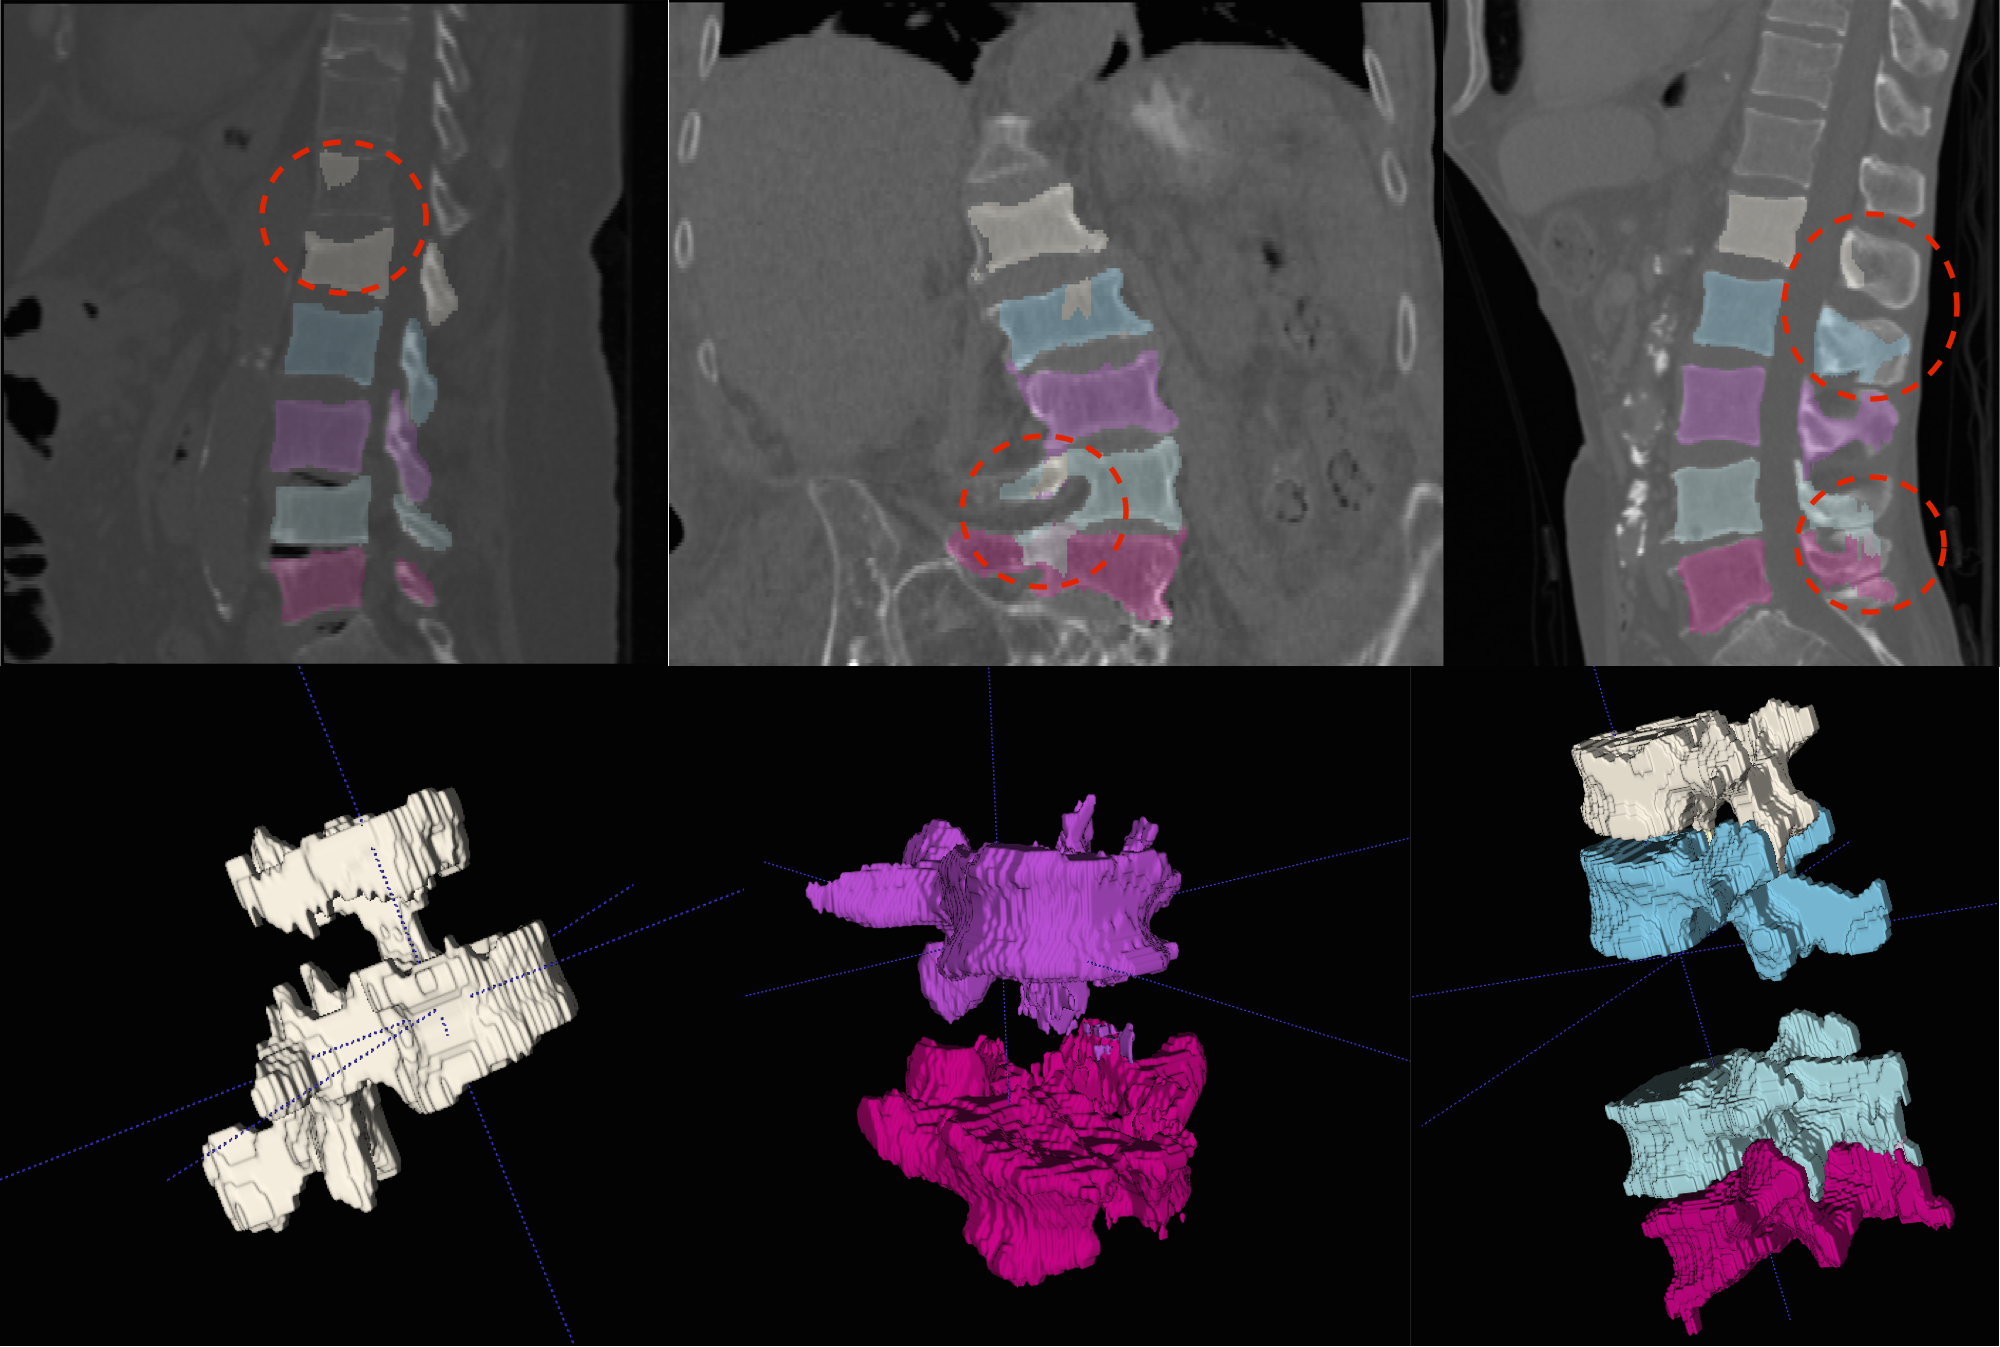

Refer to caption

(a)

(b)

Figure 5: (a) Segmented lumbar region (Row 1) with a 3D rendering of the highlighted deformities (Row 2) such as osteophytes and fractures that are successfully segmented. (b) Slightly aberrant cases: (Left) The fracture in L4-L5 is perfectly segmented. However, notice an over-segmentation in L1. (Centre) A successful segmentation of a severely scoliotic spine and deformed vertebrae. Notice some non-homogeneity in segmented labels. Also observe in 3D, a well-captured crush in L3 and an unsegmented region in L5. (Right) The anterior regions of the vertebrae are successfully segmented. However, posterior regions of L1, L2, L4, and L5 are not fully segmented.

5.1 Additional Results

We present more results of multi-class segmentation on the test set of xVertSeg (figure 5) in addition to the results in figure 4, thereby emphasising the robustness of our approach. We also present a few aberrant segmentations analysing which could further improve our approach.